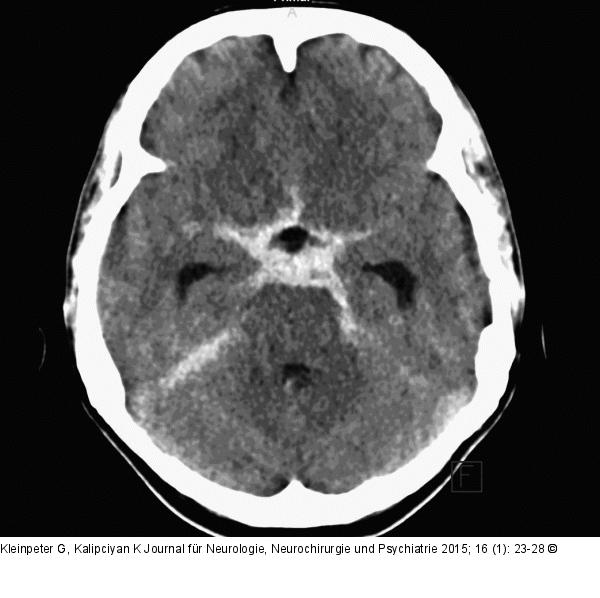

Abbildung 3: Subarachnoidalblutung Angiographisch negative Subarachnoidalblutung (nSAB). |

Angiographisch negative Subarachnoidalblutung (nSAB). |